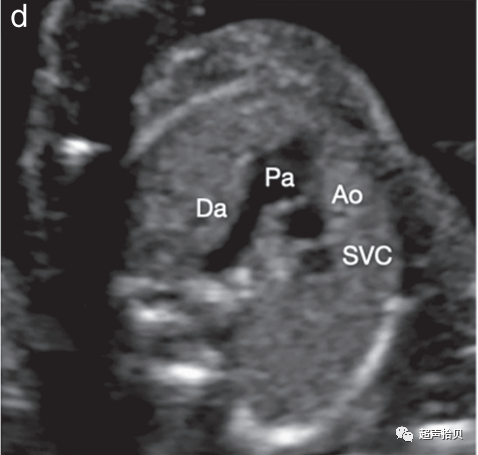

图4 用于妊娠中期胎儿心脏筛查的代表性切面。确定心脏部位,胎儿胃和胎儿心脏在同一左侧位置(未显示)。

(d)三血管切面(肺动脉(Pa)、升主动脉(Ao)和右上腔静脉(SVC))和三血管-气管切面(e)(导管弓(Da)、主动脉弓(AA)、右上腔静脉 (SVC) 和气管 (Tr)) 。

3. 三血管切面和密切相关的三血管气管切面可以改善流出道、主动脉弓和全身静脉异常的检测(图 4d、e).